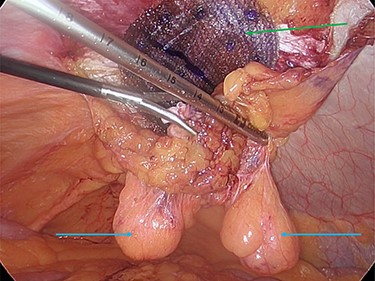

The hernia neck was closed with a 2-0 V-loc© suture (Fig. 5a and b), and a preperitoneal prolene mesh applied. The mesh was secured to the abdominal wall with an absorbable tack fixation device. The mesh was then reperitonealized with absorbable tackers (Fig. 6).

Preperitoneal mesh insertion (green arrow) and visible parietal peritoneal lipomas (blue arrows).

The decision was taken intraoperatively to leave the lipomas in situ as the hernia neck had been repaired, and it was thought that they could no longer cause any issue with pain or possible hernial reincarceration (Fig. 7).

Mesh reperitonealization and parietal peritoneal lipomas in situ (green arrows).

The hernia neck was initially closed with an absorbable suture and a preperitoneal mesh applied. The mesh was then reperitonealized and the lipomas remained exterior to this. It was felt that the lipomas posed no further risk to incarceration, given the hernial neck closure and application of a preperitoneal mesh, so they were left in situ.